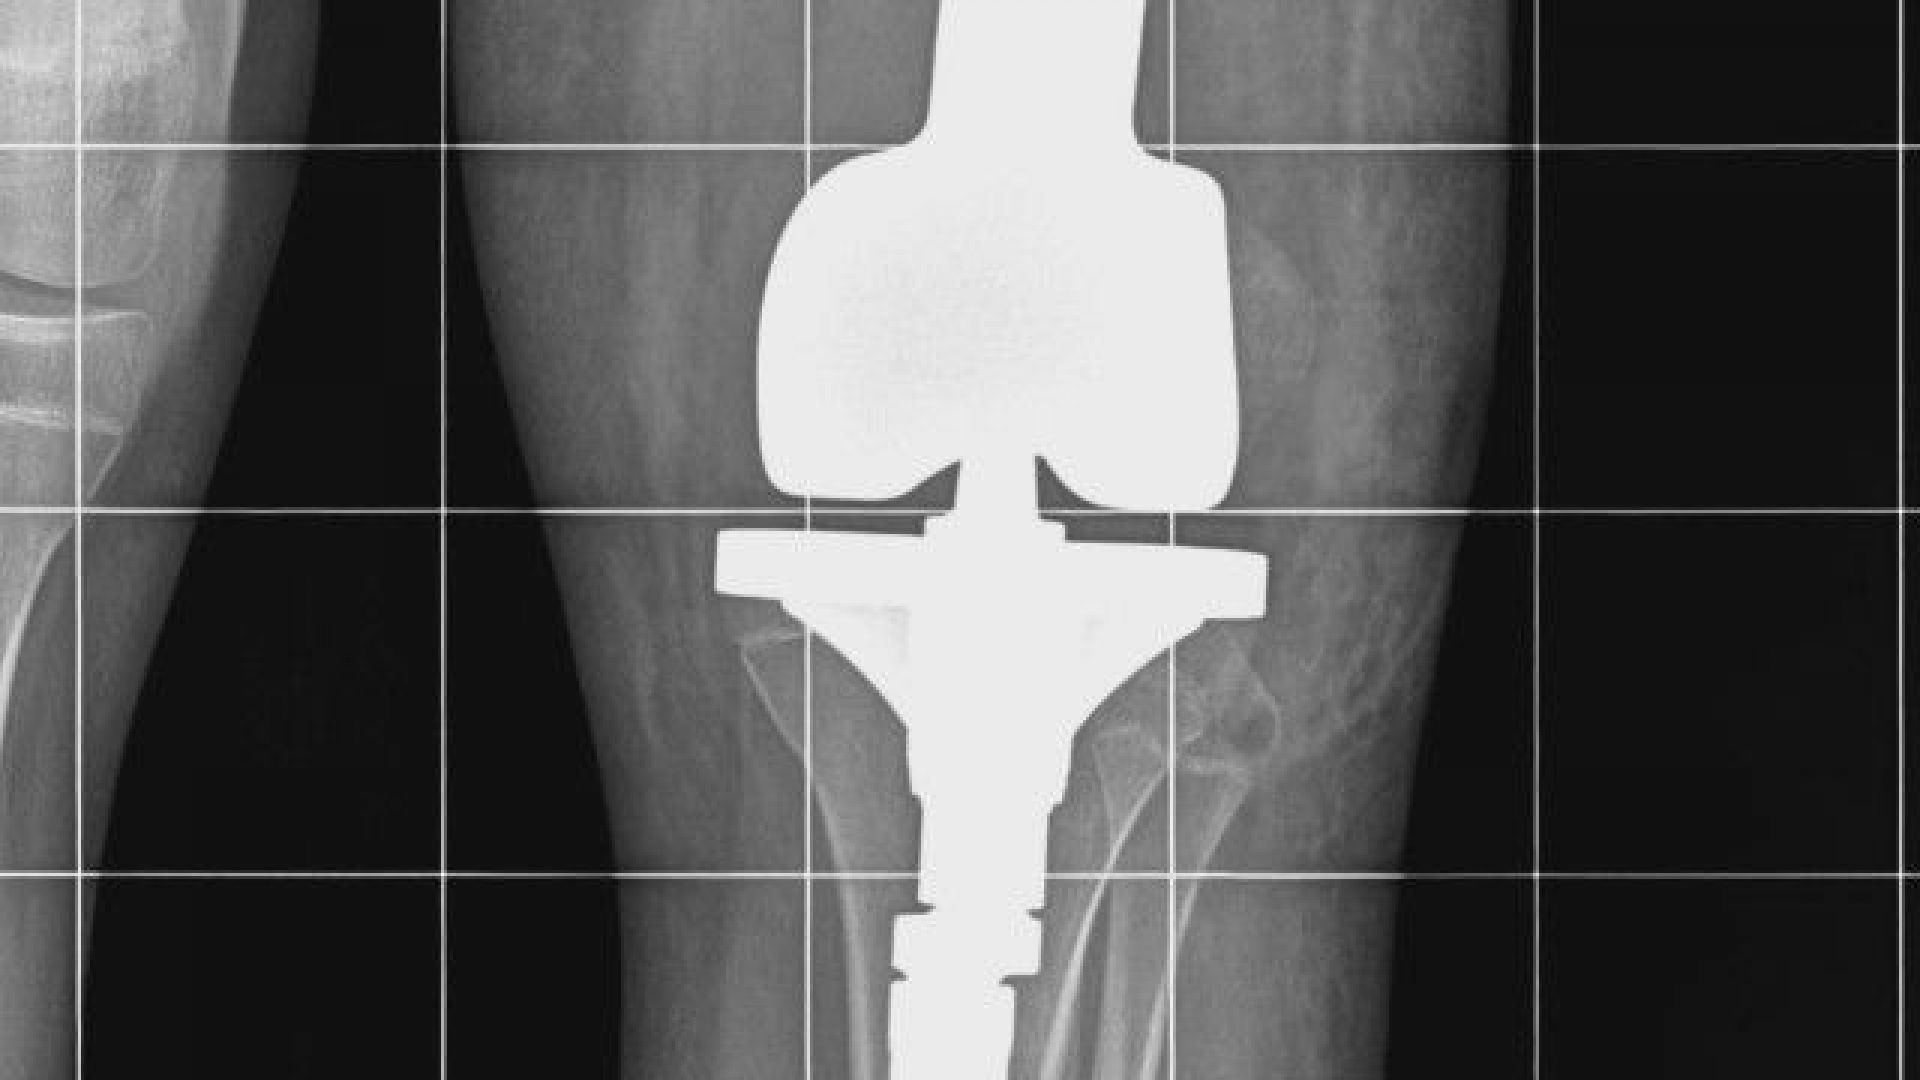

Детето постъпва в лечебното заведение с тежката диагноза Сарком на Юинг, обхващащ цялото ляво бедро. След извършена химиотерапия лекарите пристъпват към унищожаване на тумора - с цялата бедрена кост и заместването ѝ с мегапротеза.

" Тази протеза е такава, че в случай че оперираният крак изостане в растежа си, в съпоставяне със здравия крайник, след привършване на костния напредък на пациентката, ние имаме опция в избран стадий да уеднаквим крайниците, като подменим някой от модулите, които се разполагат в самия имплант ", изясни доктор Кирчо Патриков, гл. помощник в болничното заведение по ортопедия.

Протезата от 37 хиляди лева е особено направена в Германия и е платена от Здравната каса.